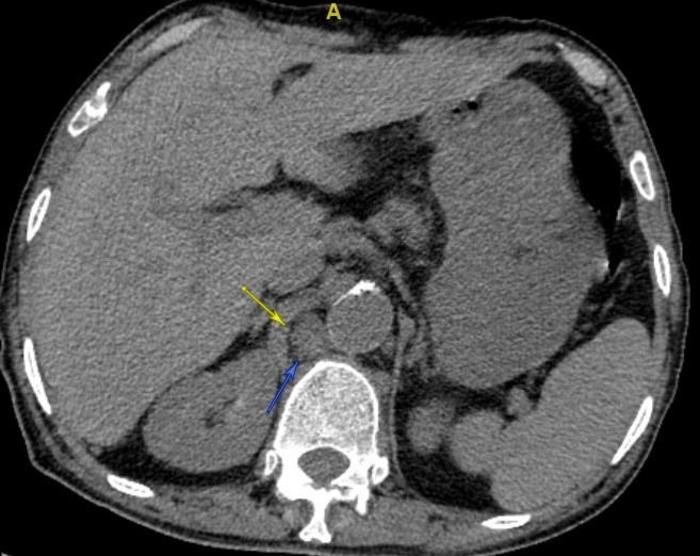

腹部的胃左淋巴结肿大,如下图。

还有腹主动脉旁淋巴结肿大,如下图。